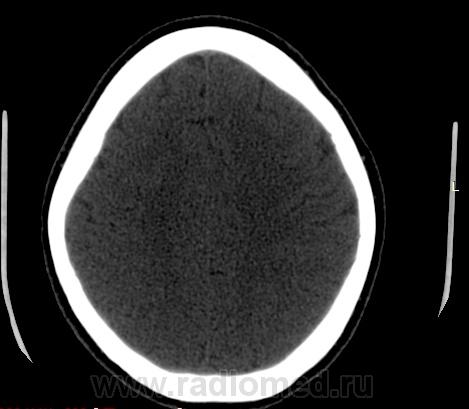

Прошу разрешить спор. По КТ - норма. Женщина, 1967г.р., жалобы на головную боль, больше в затылочной области. По-моему, не КТ-шное это дело но всеж...

Открыл. В мозгу ничего осбенного не увидел. По поводу Киари ничего не скажу, на аксиалах не вижу, а реконструкции эти срезы не строят Да и отношусь я к этой патологиии как к норме.

Аномалию Арнольда-Киари 1типа.

На МРТ выставили  аномалию Арнольда-Киари 1, нам сказали фу... На что я ответил, что по " ловцу и рыба". Во - первых, линию на КТ провести сложно ( в данном иссл.), во-вторых - естественные артефакты костей основания. И вообще пошли на...МРТ! Но осадок остался.

Для Арнольда-Киари I МРТ - как раз и есть метод диагностики, а на КТ это дело можно лишь заподозрить. Плюньте на осадок. Ну хотите, я плюну?) Тока отойдите, а то разъест))).